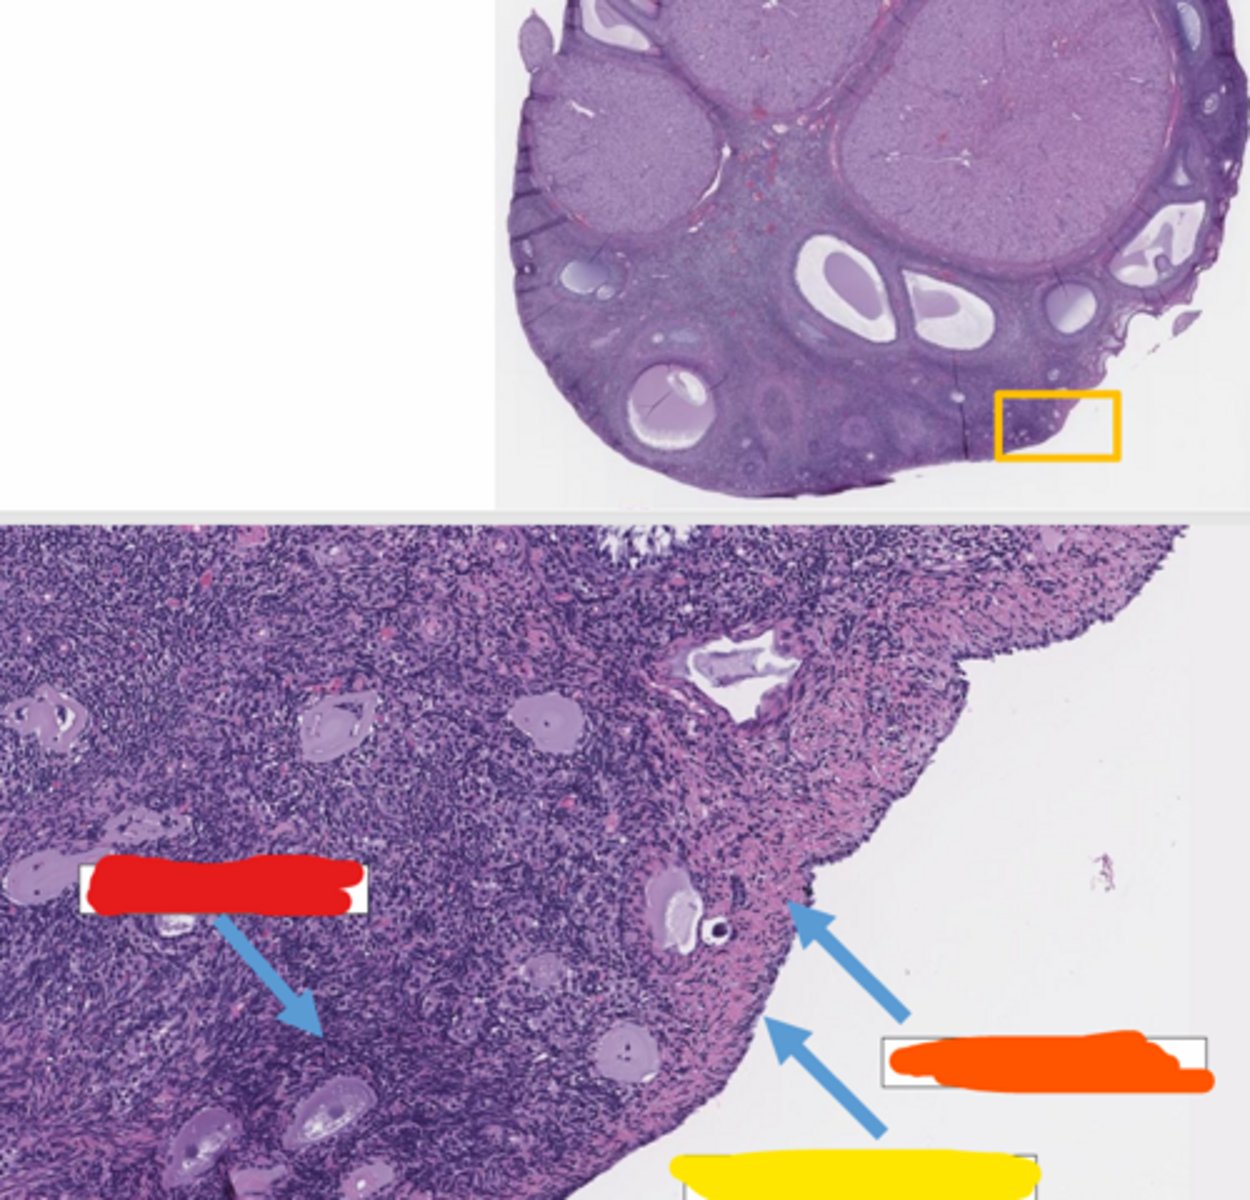

ovary

red

in dogs, the ovary has invaginations for ____

horses

in what species are the cortex and medulla inverted in the ovary?

cortex

in what part of the ovary does oogenesis occur?